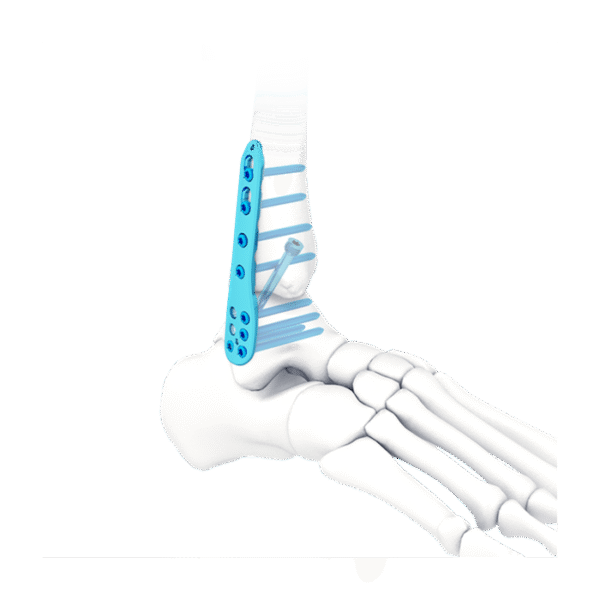

- Tres filas de orificios en el extremo distal, para fijar el calcáneo; Tornillo de fijación divergente, para mejorar la buena sujeción.

- Tres filas de agujeros en el medio, para fijar el astrágalo; tornillo de fijación divergente, para proporcionar una fijación estable

- Diseño de perfil bajo, para reducir la irritación de los tejidos blandos.

- Fusión de la articulación tibiotalar

- Fusión de tibiotalar lateral y calcáneo